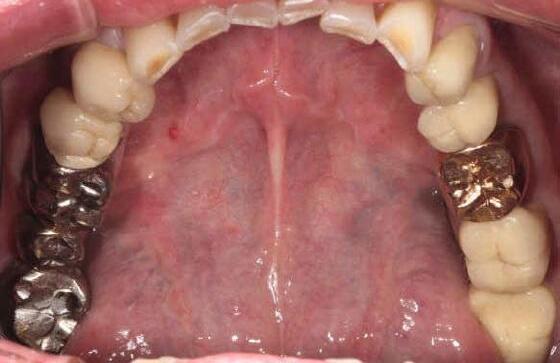

Fig 1. Patient anterior situation. Two anterior crowns fractured off.

Fig 3. Provisional restorations on central incisors and gingival images. The gingival contours were optimal, and the gingival phenotype was thick.